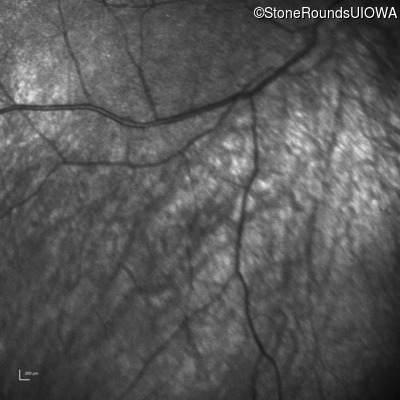

Infrared Fundus Photograph - Right -

No Light Perception

Exemplar

Expanded OCT Stack

×